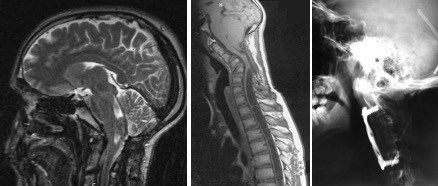

il faut en premier lieu éliminer un dysfonctionnement de valve, par l’interrogatoire, l’imagerie, le fond d’oeil, et parfois par une révision chirurgicale, avant de décider d’une intervention décompressive.

cette dernière est surtout nécessaire en cas de syringomyélie.

la craniectomie est limitée vers le haut car le torcular est abaissé; il est parfois

nécessaire de pratiquer une laminotomie de C2 pour réaliser une décompression efficace, ce qui nécessite une reconstruction et le port d’une minerve pour éviter une déformation en cyphose.

la chirurgie ne peut pas se limiter à un geste osseux ni même purement dural. lors de l’abord cisternal, on rencontre en règle une arachnoïdite dense, associée à un plexus choroïde ectopique, descendant dans le canal rachidien. il est parfois difficile, au sein de cette fibrose, d’identifier l’obex et de libérer la sortie du quatrième ventricule. il est souvent nécessaire, pour prévenir la récurrence, de mettre en place un cathéter entre le V4 et les citernes pour servir de stent.